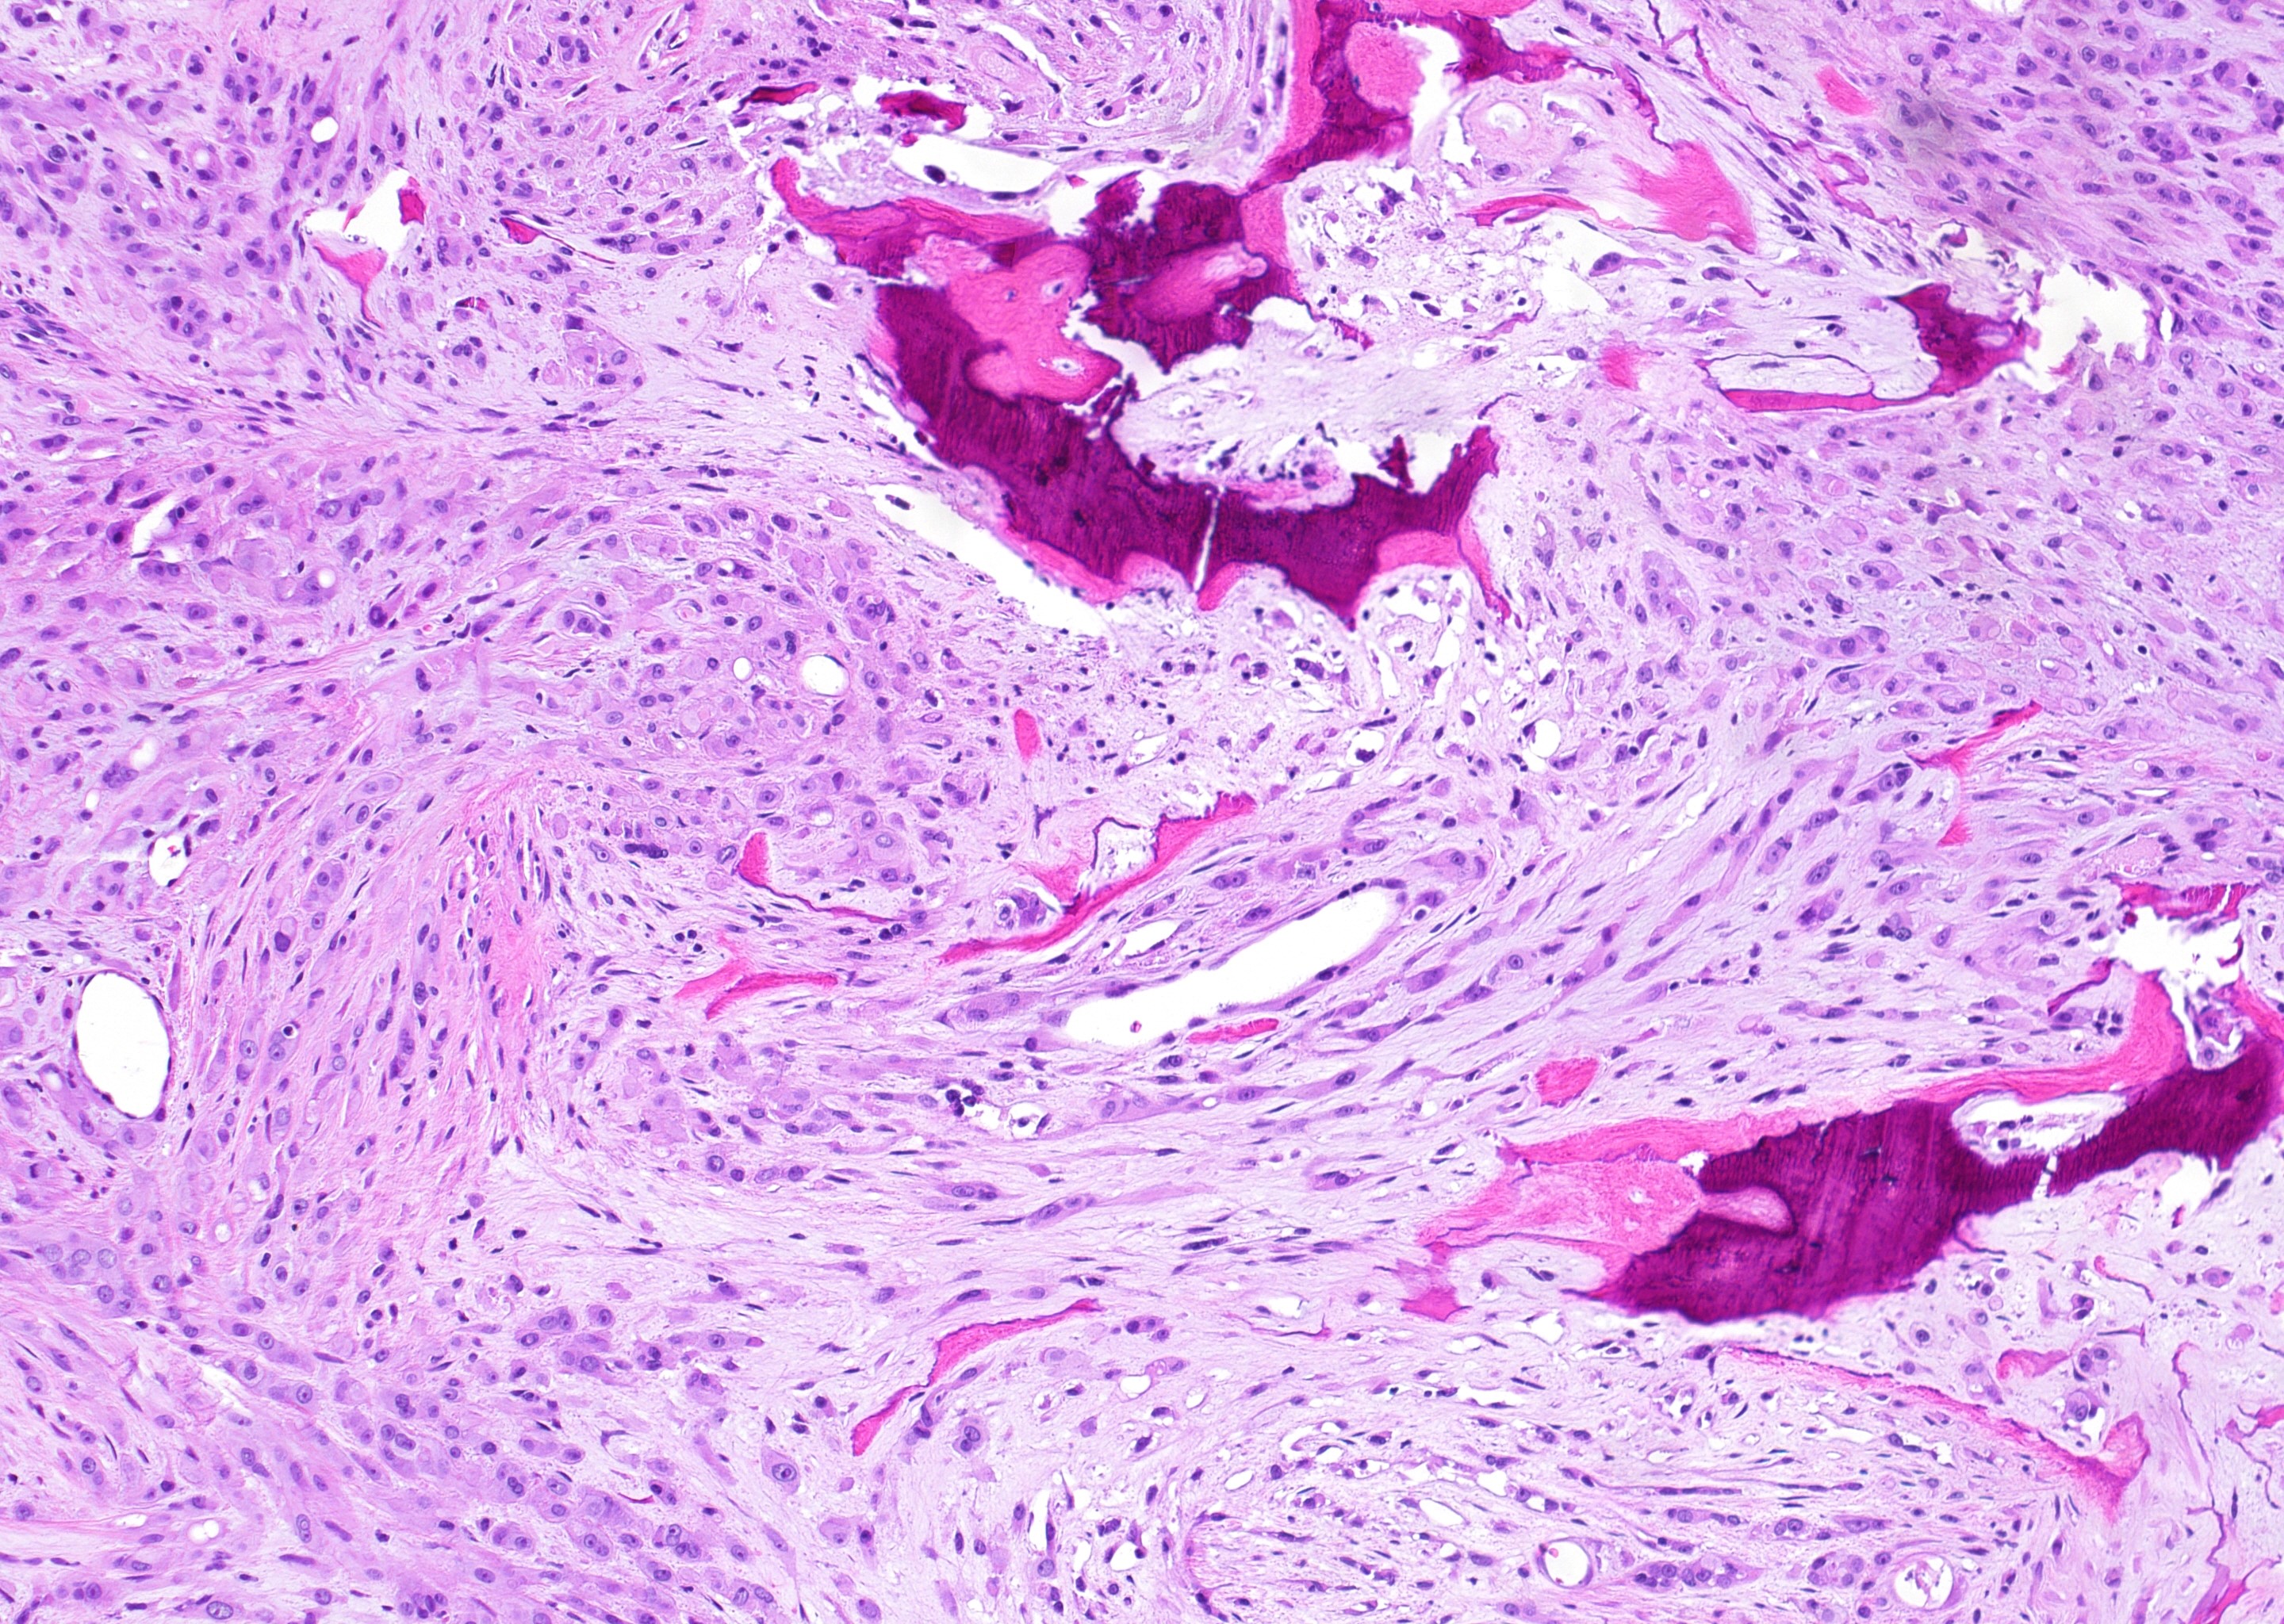

- YAP-TFE3 subtype:

- Solid nests or pseudo alveolar arrangement of epithelioid cells enmeshed in a fibrous stroma

- Tumor cells have abundant, densely eosinophilic cytoplasm and can form vascular spaces

- Intracytoplasmic vacuoles are rare

- Usually minimal mitotic activity, atypia or necrosis

Microscopic (histologic) images